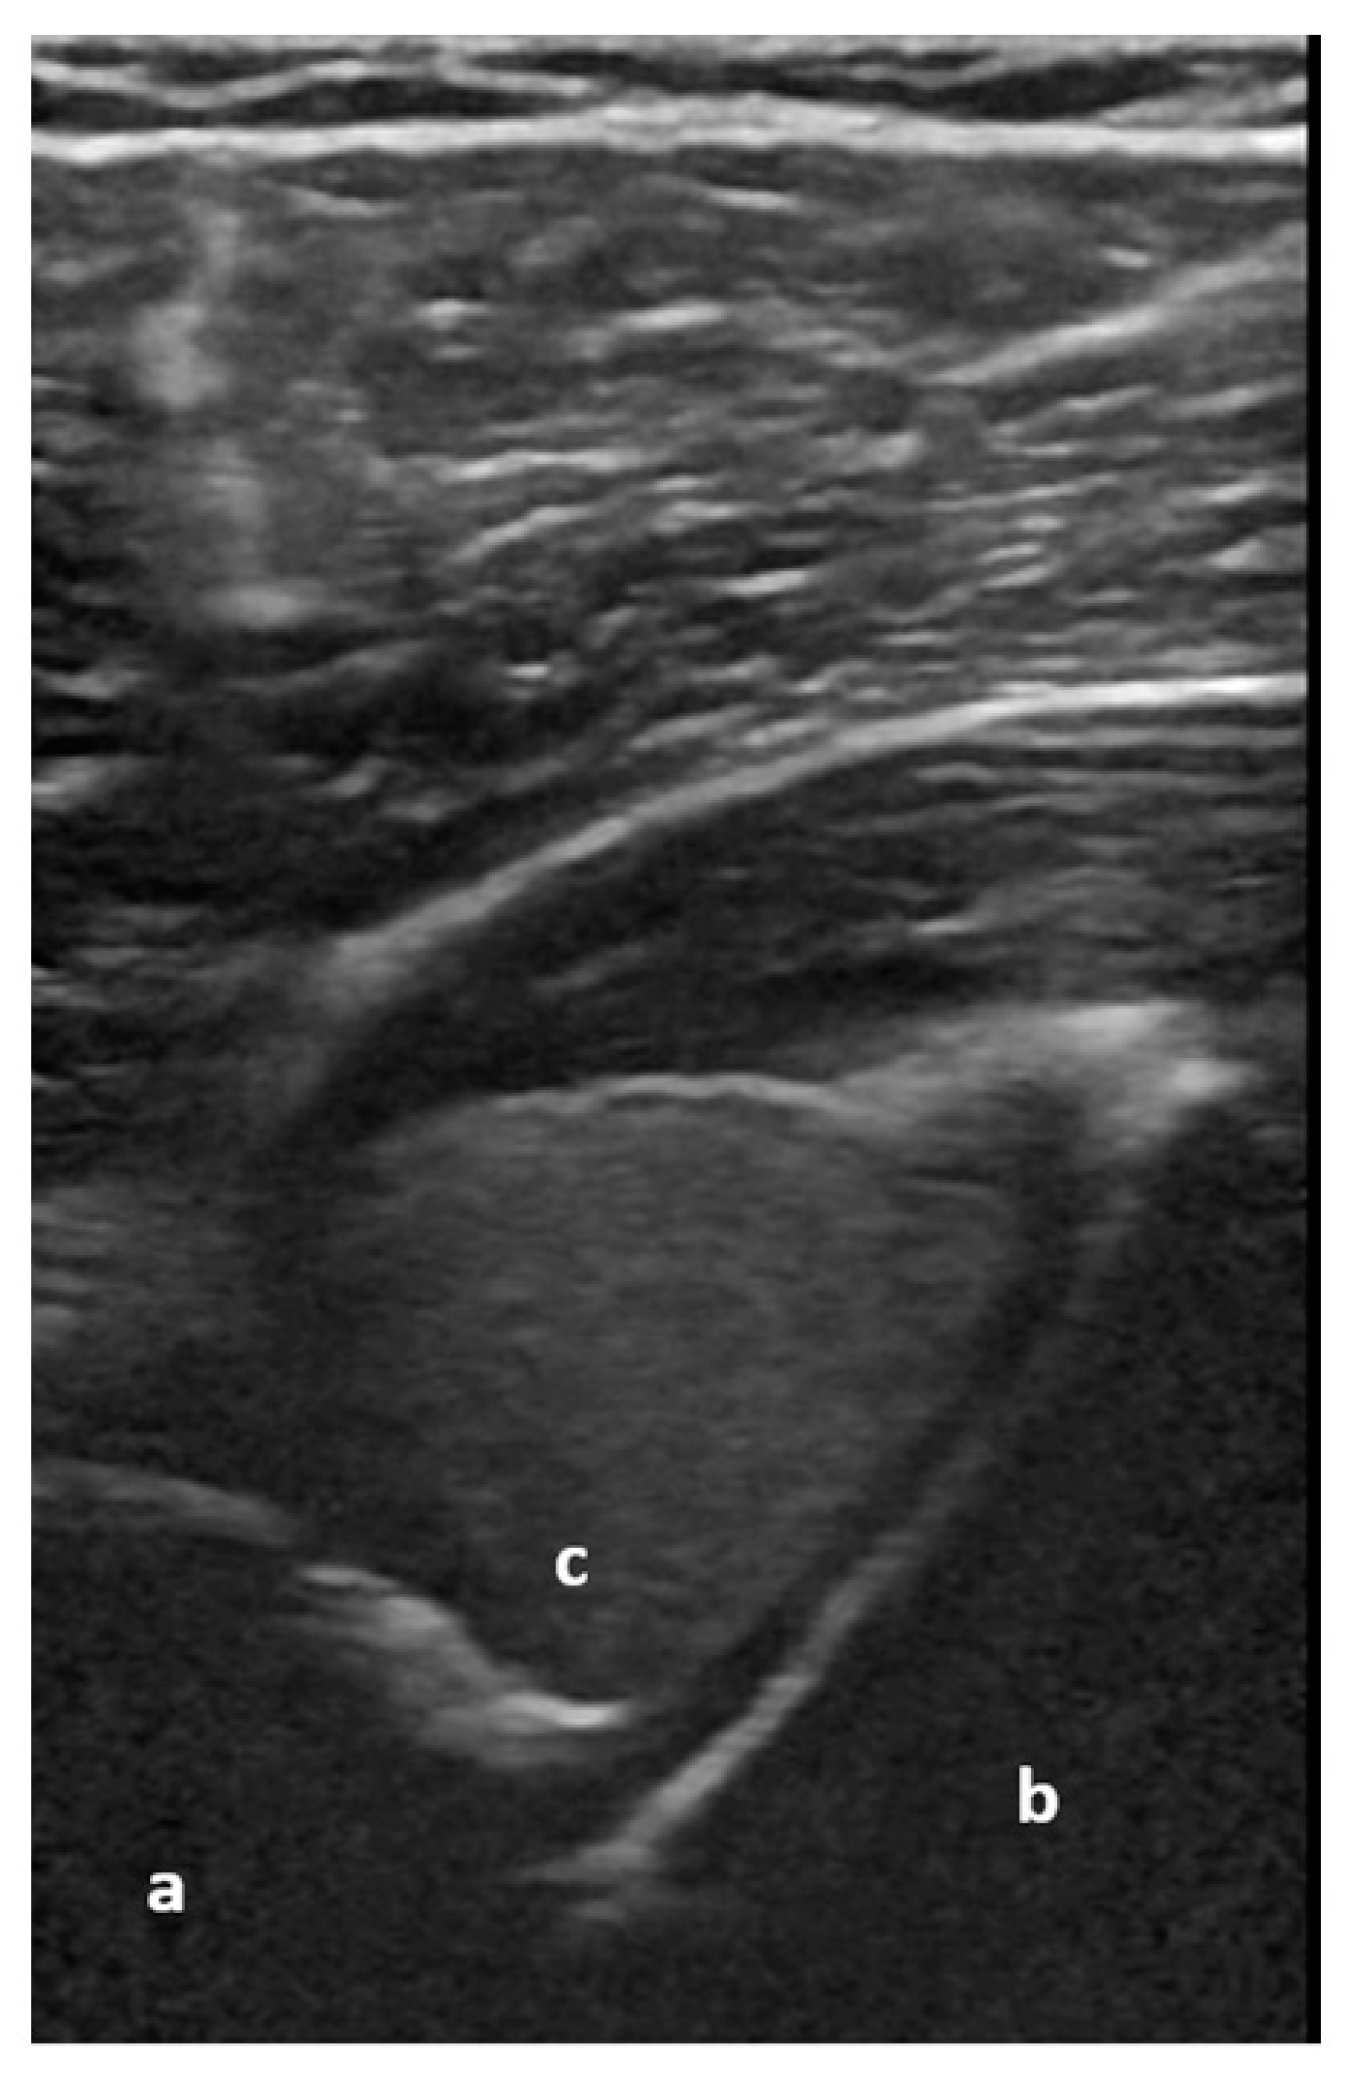

Figure 5.

Dorsal transverse view of an anteriorly dislocated humeral head (a), glenoid (b), and hemarthrosis (c). Image courtesy of J. Osterwalder.